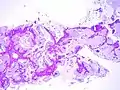

Additional images

Mucinous BAC

Non-mucinous BAC